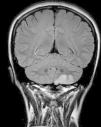

Presentamos el caso de una mujer de 31 años, que padecía migraña sin aura de localización periorbitaria, alternante, que trataba con AINE de manera puntual. No tenía factores de riesgo cardiovascular ni hábitos tóxicos, y tampoco consumía otros fármacos ni anticonceptivos hormonales. Refería que 2 meses antes su cefalea había empeorado, con episodios muy frecuentes añadiéndose finalmente vértigo y dolor occipital intenso irradiado a hombro izquierdo con adormecimiento de la extremidad superior derecha. A la exploración las constantes estaban estables, consciente y con buen estado general. No se auscultaban soplos carotídeos, cardiacos ni supraclaviculares y en el examen neurológico tan solo se objetivaba hipoestesia en extremidad superior derecha con claudicación mínima de los dedos de perfil sensitivo. En la analítica destacaba glucemia 90mg/dl, colesterol LDL 126mg/dl, homocisteína 5,9mg/dl, apolipoproteína A1 122mg/dl, apolipoproteína B100 89mg/dl y lipoproteína(a) 2,2mg/dl (valores normales). El resto de determinaciones incluyendo anticuerpos antinucleares, anticuerpos anticitoplasma de neutrófilo, factor reumatoide, anticuerpos antifosfolípido, serología de VIH, VHB, VHC, Trypanosoma cruzi y sífilis estaban dentro de la normalidad. La resonancia magnética nuclear (RMN) cerebral y la angio-RMN de troncos supraaórticos en el diagnóstico de la oclusión completa de la arteria vertebral izquierda desde su origen (fig. 1), con focos de infarto isquémico en el hemisferio cerebeloso izquierdo (fig. 2). Descartó disección arterial. Durante su estancia en la unidad de ictus no se constataron arritmias, como tampoco se evidenció cardiopatía estructural en el ecocardiograma transtorácico realizado. Fue dada de alta con recuperación completa, antiagregada con 100mg de ácido acetilsalicílico y en tratamiento con 40mg de atorvastatina al día.